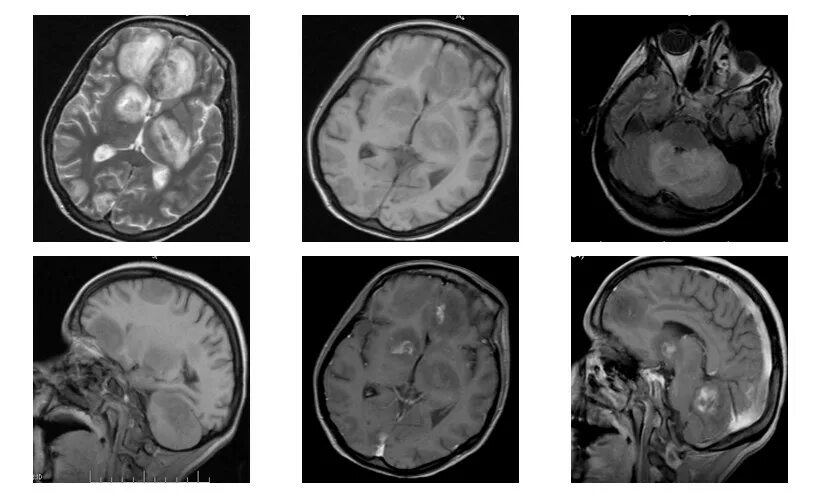

Токсоплазмоз у вич инфицированных